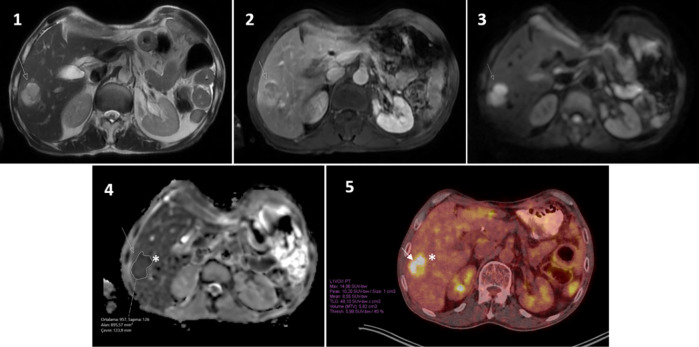

Methods: Abdominal magnetic resonance (MR) scans performed between April 2021 and 2024 using the 3T MR scanner were retrospectively evaluated. Thirty-three patients with liver metastases, less than one month between magnetic resonance imaging (MRI) and PET/CT, no treatment during this period, and lesions larger than 1 cm were included in the study. In each MRI scan, an index lesion was selected for ADC measurement. The radiologist and nuclear medicine specialist measured the same index lesion without the patient being informed of the results.

Results: The mean age of the 33 patients was 59±12 years, with 17 (51%) men and 16 (49%) women. The mean size of the index lesions was 27±9 mm. In MRI, mean ADCmin: (0.54±0.2) ×10-3mm2/s; ADCmean: (1.02±0.2) ×10-3mm2/s; ADCmax: (1.48±0.44) ×10-3mm2/s; and region of interest area was calculated as 6±4.6 cm2. In PET/CT, mean SUVmean: 5.8±3.3; SUVpeak: 6.8±4.3; SUVmax: 10.7±5.6; and metabolic tumor volume: 12.1 (7.4-20.7) cm3. No statistically significant correlation was found between ADC and SUV values.

Conclusion: There was no correlation between ADC and SUV values in liver metastases. Prospective studies with a large patient group are needed.